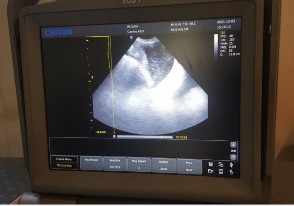

Hình 4.24. Hình ảnh siêu âm tử cung bị viêm của giống Corgi 6 tuổi

(mũi tên)